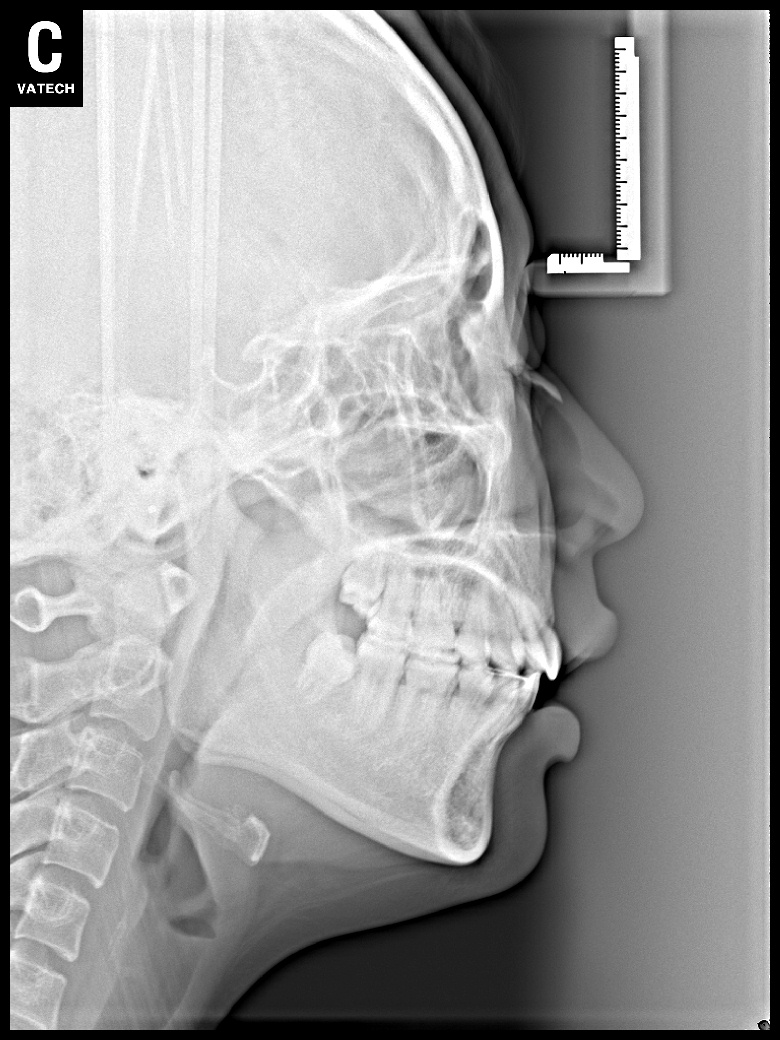

치료 후 사진입니다.